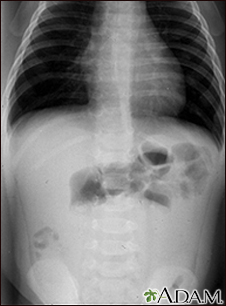

Intussusception - x-rayBackIntussusception - x-rayThis abdominal x-ray shows an intestinal condition in which a loop of bowel has slipped into another section of bowel (intussusception), causing swelling, reduced blood flow, obstruction, and tissue damage. Intussusception requires emergency treatment (barium enema or surgery) to prevent intestinal tissue death (necrosis), intestinal perforation, peritonitis, and death. E-mail FormEmail ResultsName:Email address:Recipients Name:Recipients address:Message: